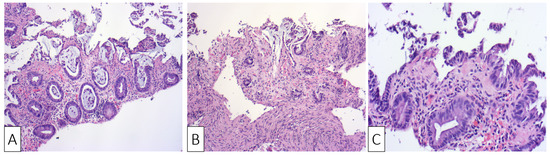

| Our patient | Male, 30 | Colicky left lower quadrant abdominal pain and bloody diarrhea | Negative fecal culture, positive toxins A, B, and GDH | Idiopathic | Several superficial longitudinal ulcerations with luminal narrowing spanning from sigmoid to the descending colon | Desquamation of superficial epithelium with focal necrosis, loss of superficial glands, edematous and necrotic lamina propria | Oral Vancomycin, symptoms resolved within two days of hospitalization |

| Okada et al., 1997 [30] | Male, 52 | Crampy lower abdominal pain followed by bloody diarrhea | Positive fecal culture and strongly positive D-1 toxin | Three-day use of Cefteram for gingivitis | Edematous mucosa with multiple longitudinal shallow ulcers, erosions, and luminal narrowing | Desquamation of superficial epithelium with crypt degeneration, fibrinous exudates in lamina propria, and mild neutrophilic infiltration | Supportive treatment, symptoms resolved by third day of hospitalization |

| Veroux et al., 2007 [31] | Female, 42 | High fever, diffuse abdominal pain with tenderness and bloody diarrhea | Positive toxins | Two weeks after renal transplant; CDI colitis was complicated by CMV colitis | Edematous mucosa with patchy erythema and longitudinal ulceration | Mucosal inflammation, hemorrhage, with leukocytoclastic vasculitis and lymphoplasmacytic perivascular infiltrate | Metronidazole and oral Vancomycin for seven days with no improvement; patient underwent subtotal colectomy but passed away two weeks later |